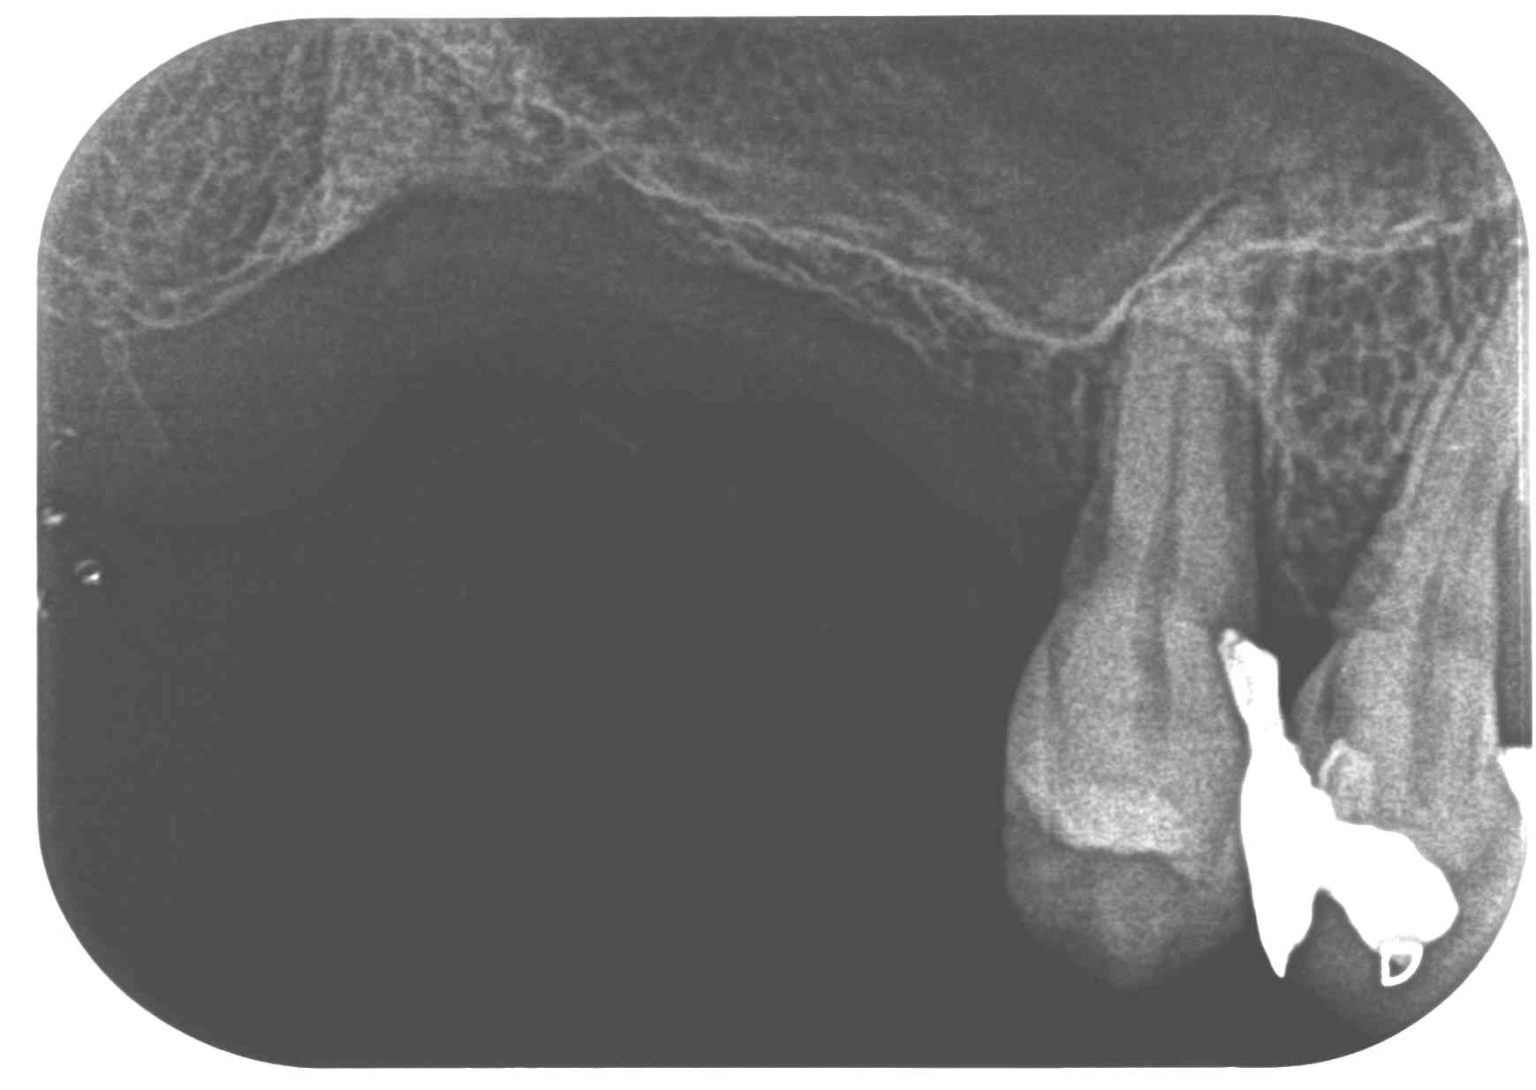

症例350代女性 主訴 左右上顎臼歯部欠損の為にインプラントを希望

治療前

治療後

※説明

上顎洞までの距離が1~2㎜と骨の高さが不足している為、洞内には人工骨(とがった砂利のような物)を使用しない方法を選択。

採血によって得られたCGFメンブレンとデンサーバーを使用し、3本共にスーパーワイドサイズのインプラントを埋入。生着までに右上は4ヶ月、左上は5ヶ月を要し、全てジルコニアにて補綴修復した。

費用 174万(オペ・ソケットリフト・採血による濃縮血小板生成・仮歯・最終補綴物まで含む)